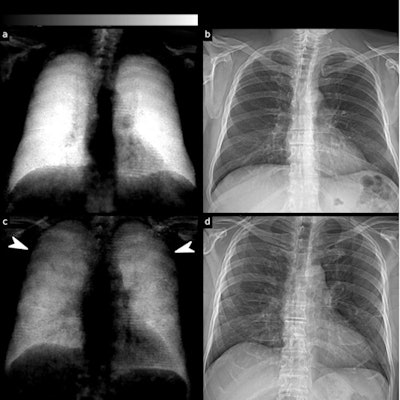

"We found that dark-field imaging has a higher sensitivity for COVID-19-pneumonia than attenuation-based imaging, and that the combination of both is superior to one imaging modality alone," wrote corresponding author Manuela Frank, a doctoral candidate in biomedical physics at TUM, and colleagues.

Overall rating values by the readers for the presence of COVID-19-pneumonia in infected patients were substantially higher for dark-field imaging (4.84) compared with attenuation-based imaging (3.16). Additionally, rating values for infected patients were higher for the combination of dark-field-based and conventional imaging (5.04) compared with dark field-based imaging alone, according to the findings.

In a receiver operating characteristic (ROC) analysis for the differentiation between infected patients and healthy subjects, the effect size expressed as area under the ROC curve (AUC) was 0.78 for standard radiographs, 0.91 for dark-field images, and 0.93 for the combination of both.